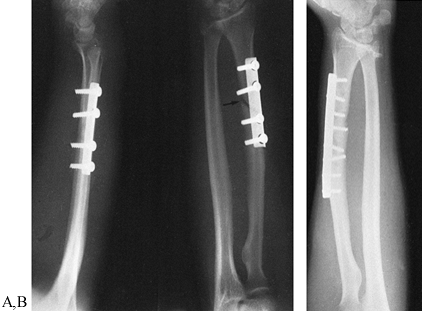

least 16 weeks and may require up to 6 months to heal solidly (Fig. 27.14 and Fig. 27.15).

Figure 27.14. Delayed union of a Galeazzi fracture. A:

An oblique fracture has been internally fixed using a semitubular plate

with inadequate cortical purchase. There is no interfragmentary screw

across the fracture. B: Union after

fixation with a 3.5 mm dynamic compression plate placed on the dorsal

radial surface with an interfragmentary screw, along with a cancellous

bone graft.

Figure 27.15. Atrophic nonunion of the ulna in a Monteggia fracture dislocation. A, B: Atrophic nonunion of the fracture of the ulna treated previously by cerclage wire and intramedullary fixation. C: A 3.5 mm dynamic compression plate and cortical cancellous bone grafting were used to stabilize the ulnar fracture. D:

After 1 year, union had occurred. Restoration of the alignment and

length of the ulna resulted in satisfactory position of the radius and

functional forearm rotation.